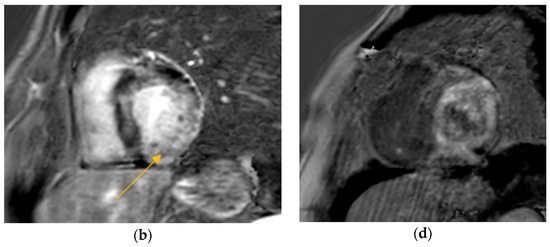

Conversely, in the cardiac sarcoidosis group, out of 92 patients, 77 had CMR, with 51 (66%) showing LGE. PET was performed in 80 patients, where intense fluorodeoxyglucose (FDG) uptake was noted in 72 (90%) of the cases, and a ‘mismatch pattern’ (FDG uptake in the same areas as perfusion defects) was identified in 40 (50%) of these patients. (Table 2).

Our study found significantly greater IVSd and LVPWd in amyloidosis compared to sarcoidosis, consistent with prior reports on echocardiographic findings in amyloidosis namely, pronounced LV wall thickening and diastolic dysfunction (Figure 1 and Figure 2). Ref [24], Conversely, TTE offers limited sensitivity in sarcoidosis, functioning mainly to prompt further diagnostic imaging when regional wall thinning or basal septal changes are detected [25]. Our CMR findings revealed focal or patchy LGE in sarcoidosis, as well as mismatch uptake patterns on PET, which parallels the existing literature that utilizes CMR for structural analysis and FDG PET for monitoring active inflammation [26,27]. Our findings in the CA cohort corroborate that PYP scintigraphy (with a negative monoclonal protein screen) remains highly specific for transthyretin cardiac amyloidosis [28]. Additionally, all 19 of our CA patients undergoing CMR exhibited a diffuse pattern of LGE, highlighting the global amyloid infiltration of myocardium in contrast to the patchy granulomatous infiltration in CS. More specific measures on CMR such as Native T1 mapping and ECV measurements can indicate the extent of amyloid infiltration [29]. Unfortunately, only 19 of the 125 amyloidosis patients underwent CMR in our study, which limited the robustness of sub-analyses in this domain (Figure 3 and Figure 4).

Figure 4.

FDG PET Imaging cardiac sarcoidosis demonstrating a perfusion–metabolism mismatch pattern, as marked by yellow arrows.